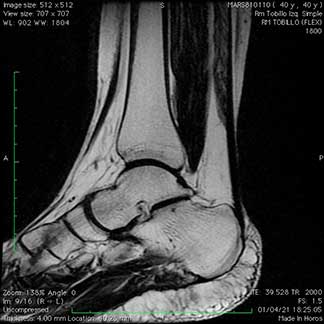

Durante mi entrenamiento en mi segundo fellow en cirugía articular y lesiones deportivas, tuve la oportunidad de hacer una rotación en el hospital CEMA by FIFA (Centro de Excelencia Médica en Altura) en Pachuca Hidalgo, donde brindé atención médica y quirúrgica en las instalaciones de la Universidad a pacientes deportistas profesionales y de alto rendimiento, miembros del equipo de fútbol “Tuzos de Pachuca”.

Galería